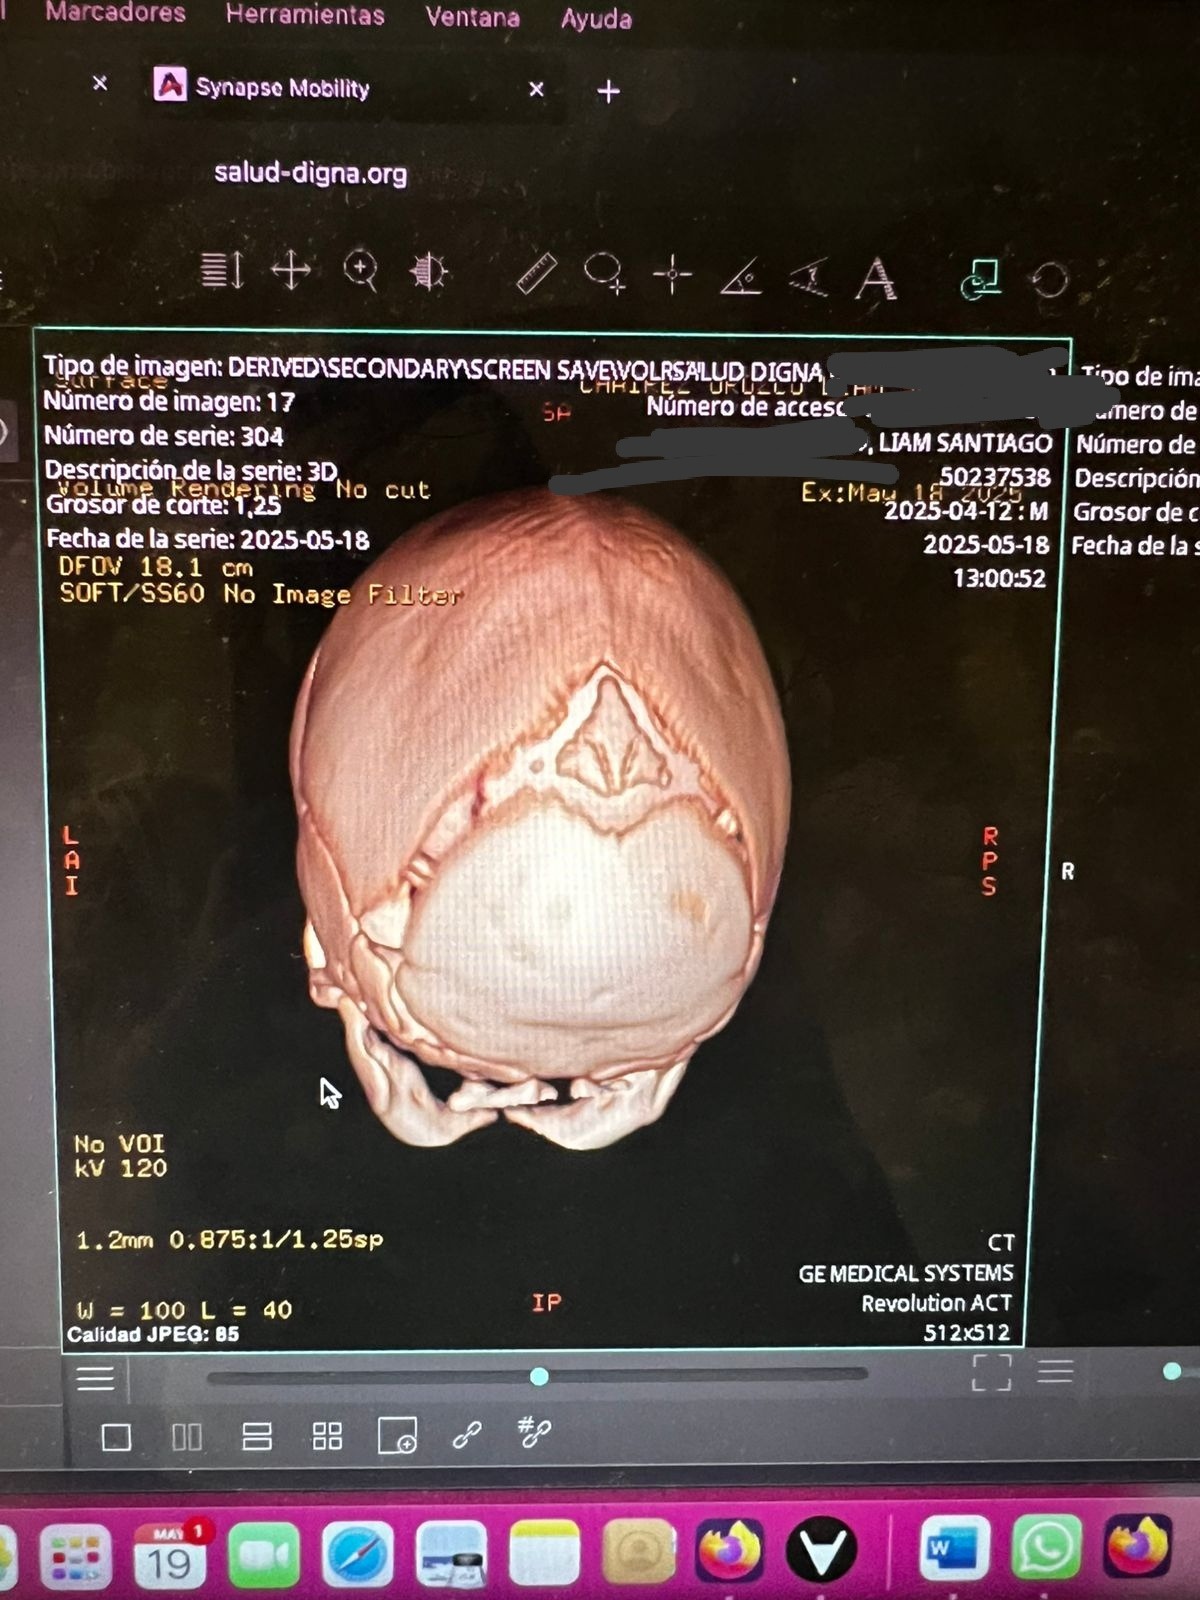

Hola mi nombre es Diana y hace aproximadamente un mes nació mi sobrino Santiago, ayer le acaban de detectar craneosinostosis y es necesario realizarle una cirugía en su cabecita lo más rápido posible para que su cerebro pueda tener un desarrollo adecuado, para realizar esta cirugía en los hospitales públicos hay lista de espera de seis meses aproximadamente y debido a la urgencia y que vamos contra reloj ya que se debe realizar en los primeros meses de vida que es cuando es menos riesgosa la operación por eso la única opción que nos queda es realizarla en un hospital privado por eso el costo tan elevado, les pido de todo corazón su ayuda cualquier aportación es de gran ayuda para poder juntar el dinero cuanto antes y el pequeño Santi pueda ser operado cuanto antes.